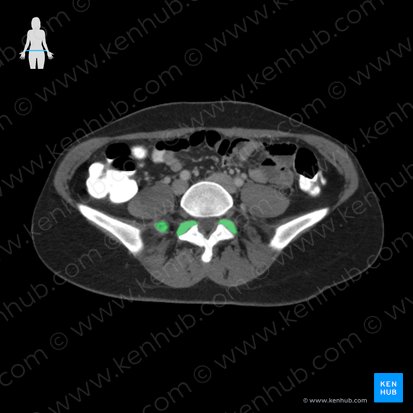

Kreuzbein (Os sacrum)

Das Kreuzbein (Os sacrum) ist ein dreickiger Knochen, der zum unbeweglichen Teil der Wirbelsäule gehört.

Es dient als Verbindungsstelle zwischen Wirbelsäule und Becken und schützt die kaudalen Spinalnerven des Rückenmarks.

Zu Beginn besteht das Kreuzbein aus fünf Kreuzbeinwirbeln (Vertebrae sacrales, S1-S5), die im Laufe des Lebens zu einem großen Knochen verschmelzen.

Die ventrale Fläche des Kreuzbeins (Facies pelvica) ist konkav gekrümmt, die dorsale Fläche (Facies dorsalis) konvex. Die Krümmung in der Sagittalebene nach hinten wird auch als Sakralkyphose bezeichnet.